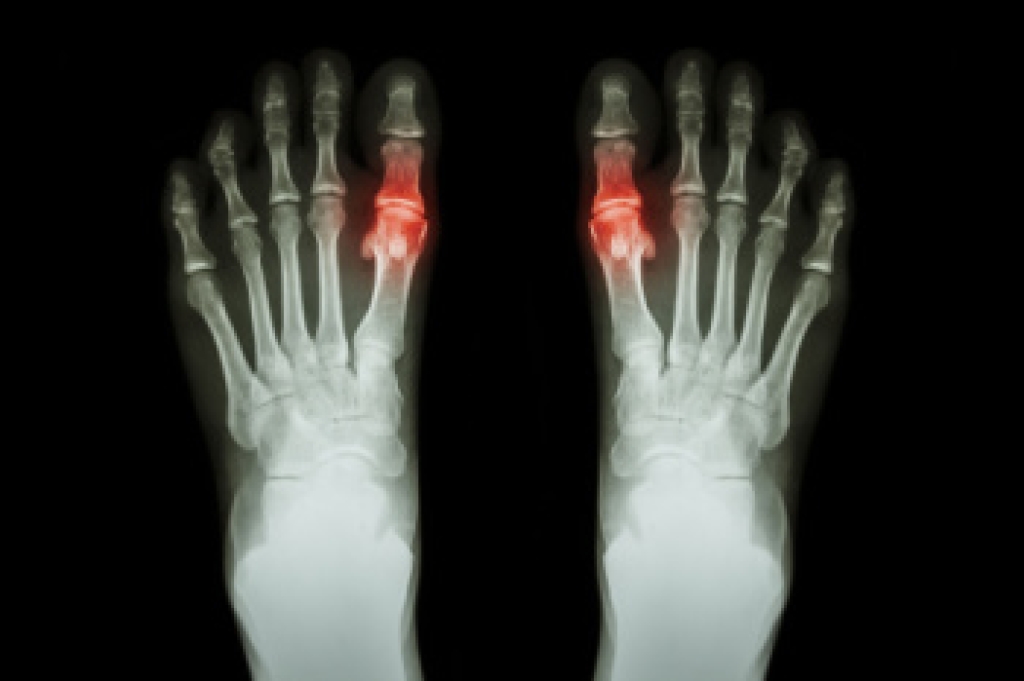

Gout is a form of inflammatory arthritis caused by the buildup of uric acid crystals in the joints, often affecting the big toe. This buildup, known as hyperuricemia, occurs when the body produces too much uric acid or fails to eliminate it efficiently. Common causes include a diet rich in purines, kidney dysfunction, or certain medications. Symptoms involve sudden and intense big toe joint pain, redness, swelling, and warmth. Diagnosis is made through blood tests, imaging, or joint fluid analysis. A podiatrist can help manage gout flares, recommend footwear modifications, and offer strategies to reduce pressure on affected joints. If you have had one or more gout attacks, it is suggested that you are under the care of a podiatrist who can help you to manage this painful condition.

Gout is a form of arthritis that is characterized by sudden, severe attacks of pain, redness, and tenderness in the joints. The condition usually affects the joint at the base of the big toe. A gout attack can occur at any random time, such as the middle of the night while you are asleep.